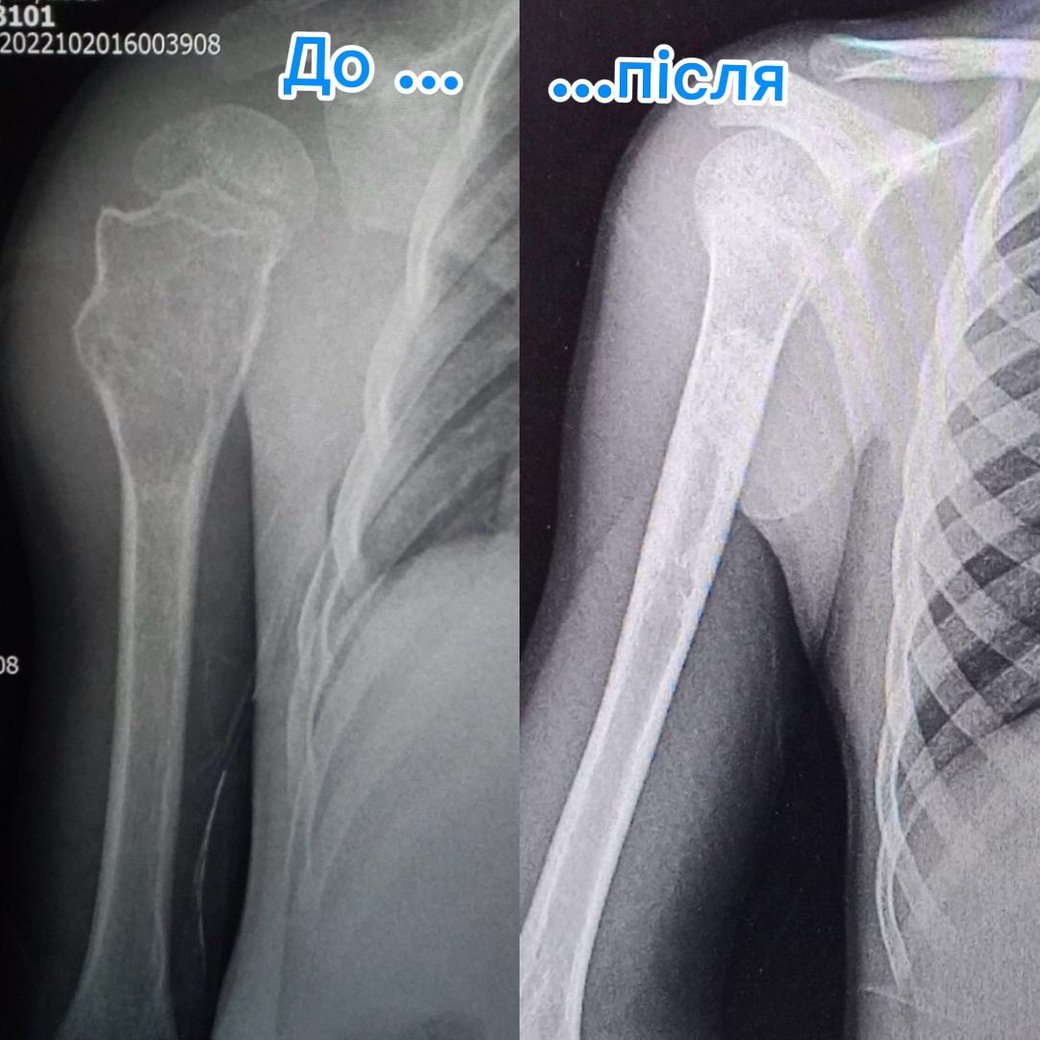

Під час рентгену медики виявили велику кісту у плечовій кістці. Лікарі обрали щадний метод лікування — пункції замість складної операції.

Хлопчику тричі, з інтервалом у три місяці, під загальним наркозом промивали кісту та вводили у неї спеціальний препарат.

У лікарні кажуть, що цей метод дозволив уникнути великого хірургічного втручання. Зараз у дитини повністю відновилися рухи в плечі, і вона повернулася до активного життя.